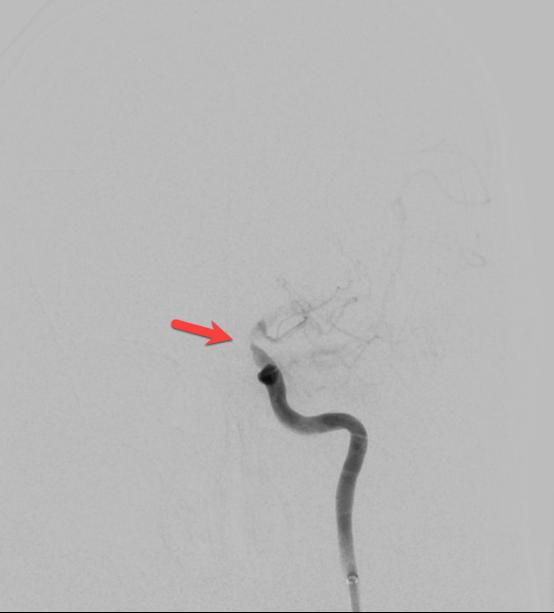

在转运的过程中,患者症状持续加重,完全失语、右侧肢体全瘫同时意识逐渐模糊。糟糕,一定是左侧颈内动脉闭塞后血流缓慢继发颅内血栓形成。时间就是大脑,为挽救李大哥的生命,民航总医院卒中团队高效运作起来,神经内科、血管介入科、麻醉科迅速完成了患者的转运、麻醉及造影。如术前所料,患者左侧颈内动脉C6段闭塞(图4、5),左侧大脑中动脉M2段血栓形成(图6)。一个一个环环相扣的动作,一个一个精细无间的配合,血管介入科团熟练的完成了取栓支架就位(图7)、取出大脑中动脉血栓、植入颈内动脉支架(图8)等一系列操作,成功的开通了血管,恢复了颅内的血流(图9、10)。

图4

图5